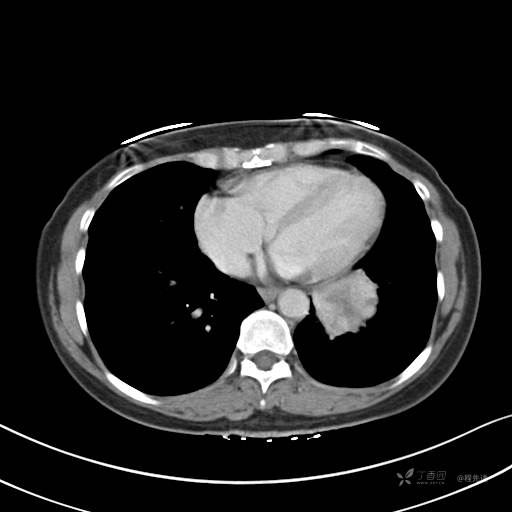

增强动脉期

动脉期CT值约74HU